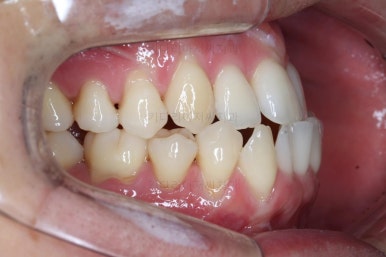

부산비수술교정 키다리아저씨치과에서 시행한 이번 치료의 결과입니다.

옆모습이 주걱턱 느낌이 많이 없어졌고 볼록하던 아랫입술도 뒤로 들어갔어요. 앞니가 거꾸로 물리지 않게 되어 웃거나 말하는 모습도 자연스러워졌어요.

아랫니 갯수가 모자라고 중앙이 맞지 않았고 짝이 안맞는 상황이었으나 비교적 잘 마무리를 했어요.

거꾸로 물리는 상황이 개선되었기 때문에 앞니나 어금니의 교합은 이전과 비교할 수 없을만큼 좋아졌지요.

전후 모습을 비교해 보겠습니다.

왼쪽이 치료 전, 오른쪽이 치료 후 모습입니다.